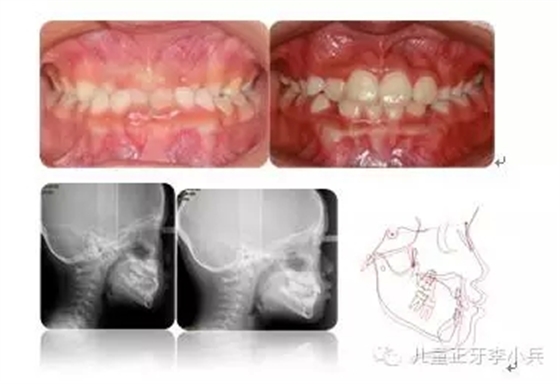

4.III類骨性畸形的早期矯治:傳統(tǒng)的功能矯形概念是在兒童青春發(fā)育高峰前期開始。對(duì)于骨性III類的矯形治療的開始時(shí)間,國(guó)內(nèi)外一直存在爭(zhēng)議。華西兒童早期矯治??圃诳偨Y(jié)本科III類骨性矯治的療效后,認(rèn)為III類骨性的矯形矯治在第一橫磨牙萌出時(shí)(6歲)開始必在青春發(fā)育高峰前期(9歲)時(shí)開始能得到更多的骨性改變。(圖5,III類骨性的早期功能矯形治療)必須強(qiáng)調(diào)的是,早期功能矯形治療必須保持到恒牙列初期(12歲)以維持矯形治療的效果,避免由于遺傳的影響造成的矯形治療的復(fù)發(fā)。

圖 5 骨性III類錯(cuò)合的早期矯治,保持持續(xù)到兒童發(fā)育結(jié)束;